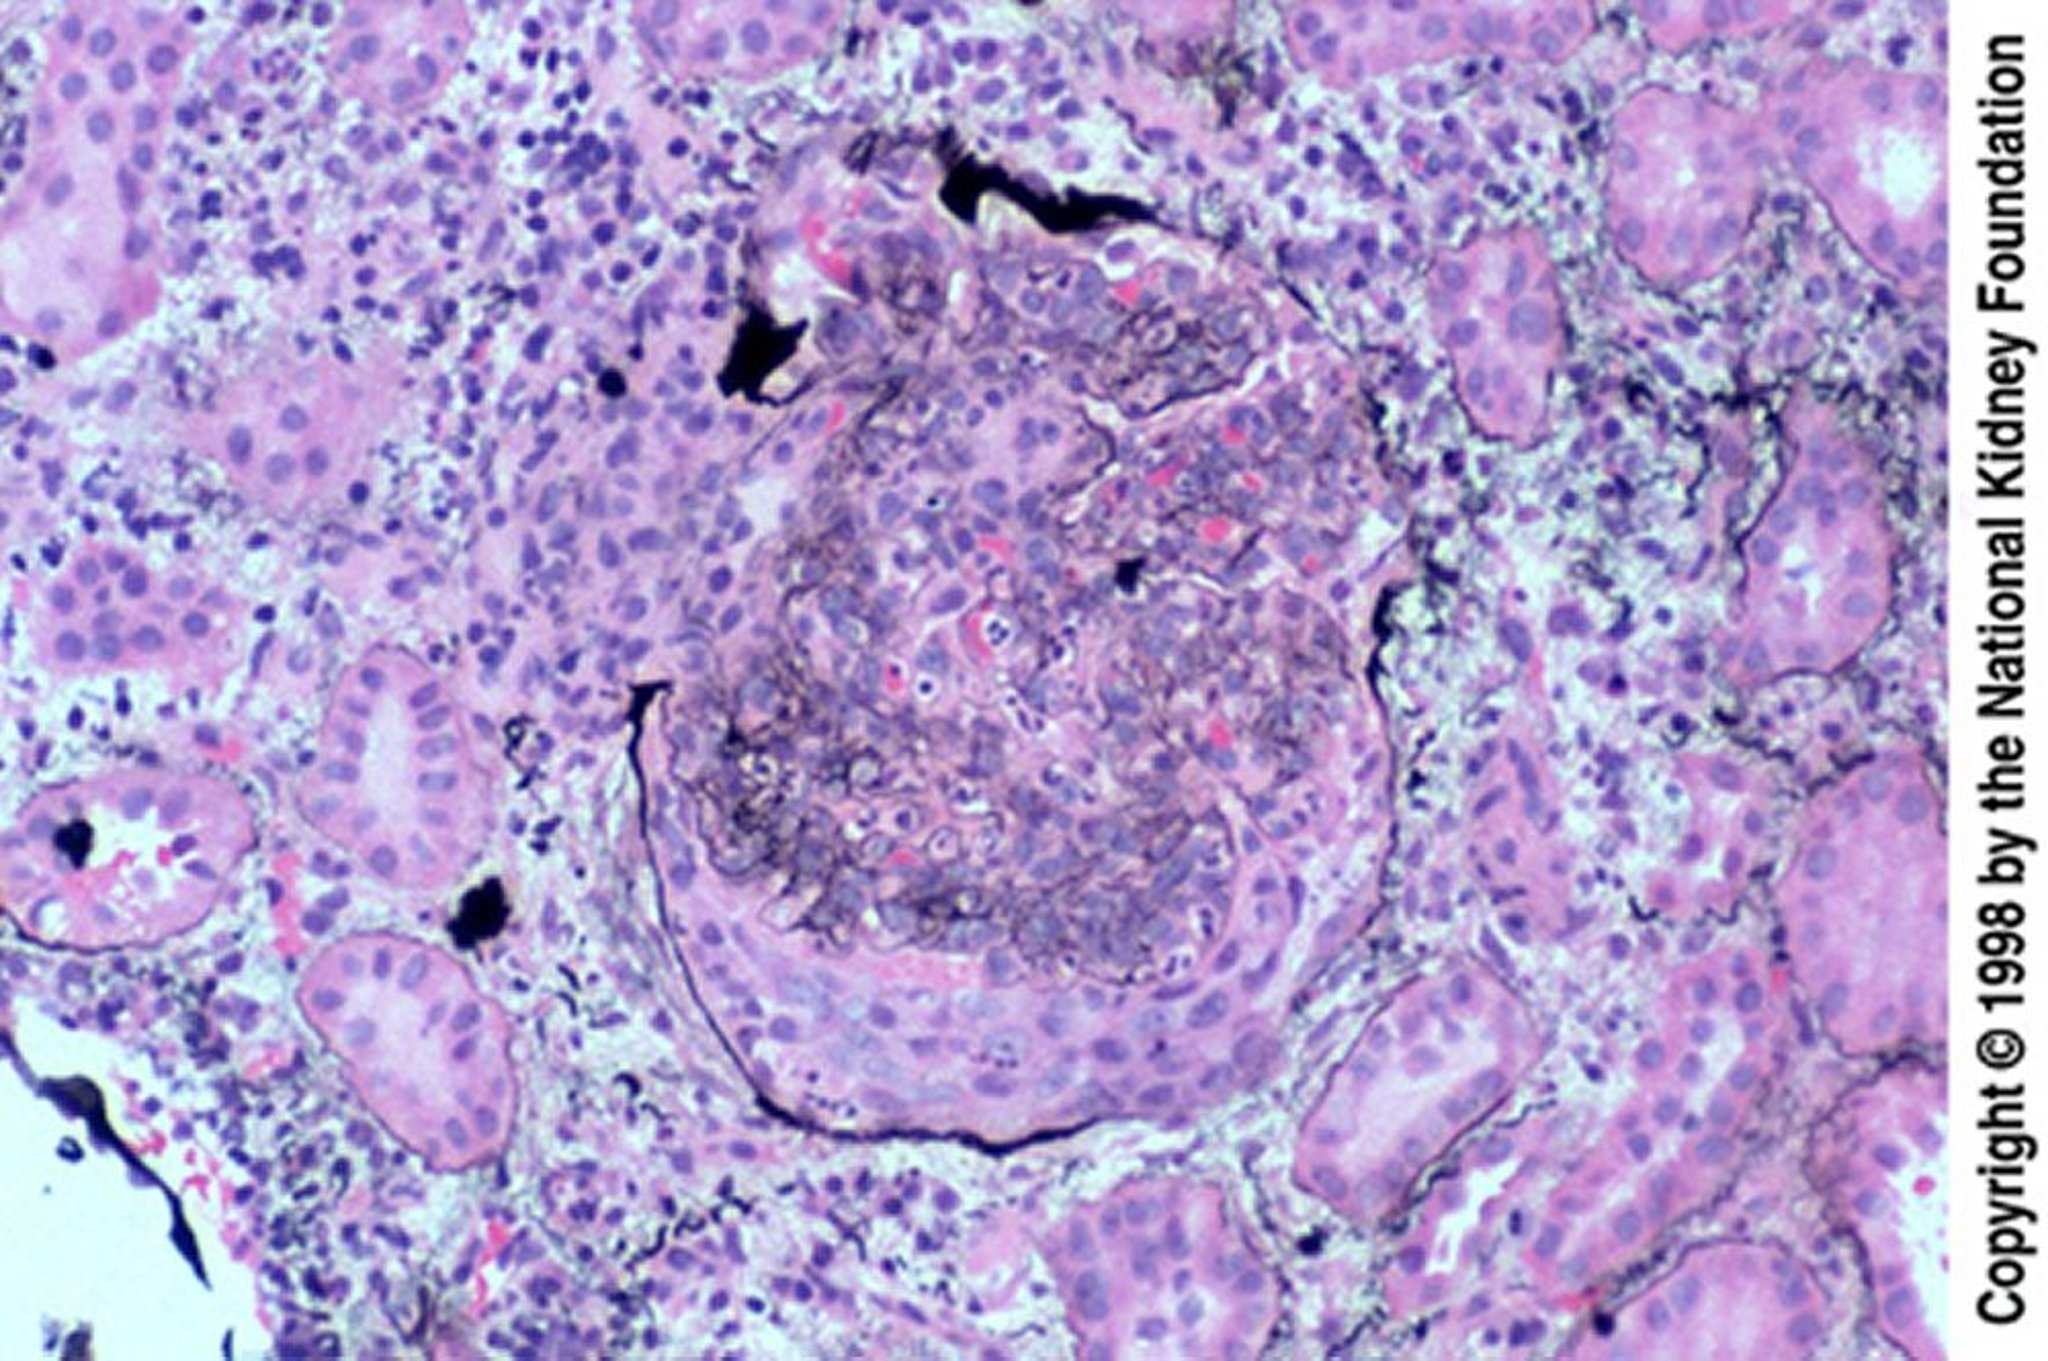

Glomerulonefrite postinfettiva (semilune epiteliali)

Le semilune epiteliali sono particolarmente frequenti quando la biopsia viene eseguita tardivamente, dopo una mancata risposta al trattamento. La semiluna ha rotto la capsula di Bowman (colorazione all'argento di Jones, ×200).

Imagine fornita da Agnes Fogo, MD, and the American Journal of Kidney Diseases' Atlas of Renal Pathology (vedi www.ajkd.org).